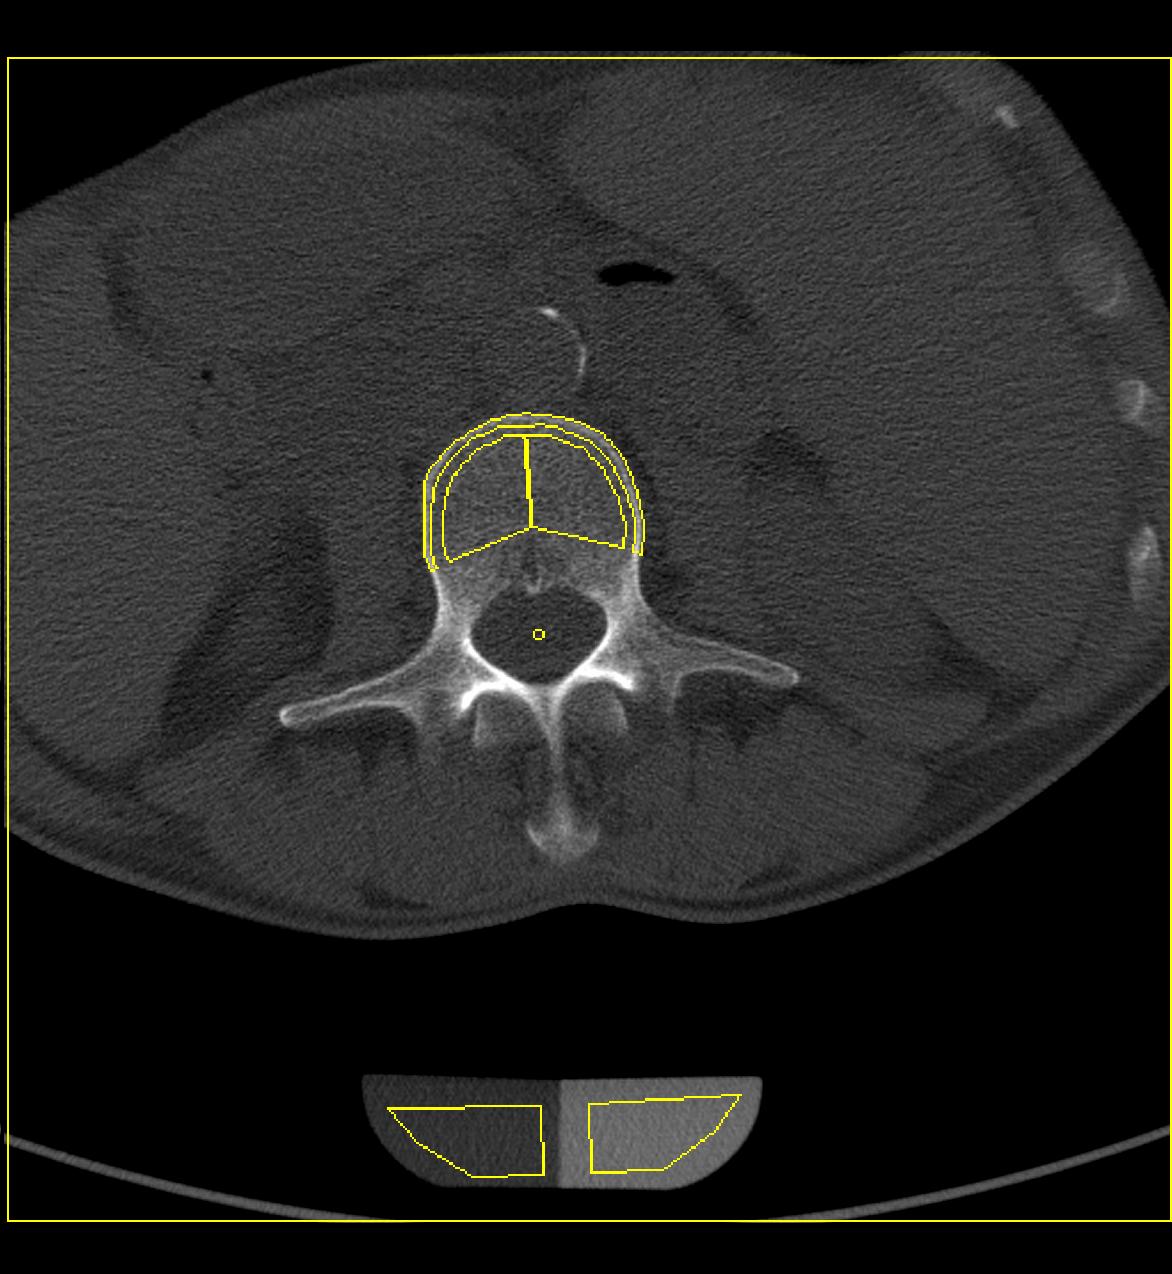

In der Klinik für Diagnostische und Interventionelle Radiologie und Nuklearmedizin wird die lokale perkutane Tumorablation durch Radiofrequenzablation oder Mikrowellenablation durchgeführt. Dabei handelt es sich um Verfahren, bei denen in einem vorher definierten Bereich des Körpers Gewebe durch die Zufuhr von großer Hitze zerstört wird. Klassischstes Beispiel ist die lokale Zerstörung einer bösartigen Raumforderung. In den erwünschten Zielgebieten entstehen sog. Hitzenekrosen oder Koagulationsnekrosen. Antrieb für die starke Hitzeentwicklung ist eine Form von Hochfrequenzstrom bzw. ein Mikrowellengenerator, ähnlich dem Verfahren wie es heute auch beim Veröden von Gefäßen im Rahmen von Operationen genutzt wird. Oberstes Ziel ist es, eine möglichst große Koagulationsnekrose zu erzeugen, ohne dabei dem restlichen Organismus in irgendeiner Weise zu schaden. Wir verwenden für die Radiofrequenzablation bei uns ein System mit sehr dünnen Aufspreizelektroden und einem leistungsstarken 460 Kilohertz-Generator (Video). Bei diesem technischen Verfahren erreicht man Spitzenleistungen von 250 Watt. Der Mikrowellenablator stimuliert Wassermoleküle. Dabei entsteht kinetische Reibung und Hitze, die das Gewebe verkocht. Verschiedene Wellenlängen erzeugen einen unterschiedlichen Wirkungsradius und damit auch einen unterschiedlichen Hitzeradius.

Etwa 2,5 cm bis 3,5 cm große Gewebsbereiche lassen sich pro Elektrodenposition mit beiden Varianten zerstören. Nach etwa einer Viertelstunde ist das Gewebe im Bereich der eingebrachten Ablationssonde vollständig zerstört. Während einer Ablation wird mit Hilfe einer computertomographischen Untersuchung stets die Lage der Sonde kontrolliert, um eine Zerstörung von gesundem Gewebe zu vermeiden.